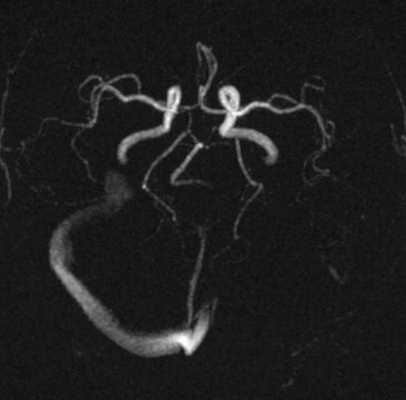

Исключали клинически значимую кардиологическую и лёгочную патологию. Обработку полученных данных проводили при помощи пакета статистических программ SPSS 10 с использованием критериев Стьюдента и Манна - Уитни. Результаты и их обсуждение. Учёт венозной фазы кровотока при МРТ-реконструкции сосудов головного мозга позволил верифицировать варианты развития поперечного и сигмовидного венозных синусов в виде их гипоплазии (рис.1) и полной аплазии (рис. 2).

Рис. 1. МРТ-визуализация сосудов головного мозга с венозной фазой мозгового кровотока. Гипоплазия левого сигмовидного и поперечного венозных синусов головного мозга. Существенное снижение кровотока в левых сигмовидном и поперечном синусах. Асимметрия кровотока в яремных венах - 86 и 14 %

Рис. 2. МРТ-визуализация сосудов головного мозга с венозной фазой мозгового кровотока. Отсутствует кровоток в левых сигмовидном и поперечном синусах. Асимметрия кровотока в яремных венах - 98 и 2 % (аплазия синусов)